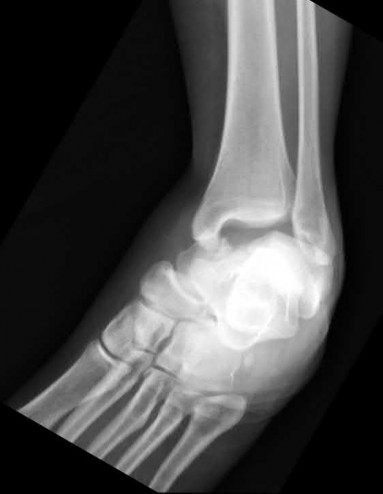

A 28-year-old male sustains a severe hyper-dorsiflexion injury to his ankle in a motor vehicle accident, resulting in a Hawkins Type III talar neck fracture. Which of the following arteries provides the predominant blood supply to the body of the talus, placing it at significant risk for avascular necrosis in this injury?

Options:

Correct Answer: Artery of the tarsal canal

Explanation:

The artery of the tarsal canal, which is a branch of the posterior tibial artery, provides the dominant blood supply to the talar body. In a Hawkins Type III fracture (talar neck fracture with subtalar and tibiotalar dislocation), the blood supply from the artery of the tarsal canal, the artery of the sinus tarsi, and capsular vessels are disrupted, leading to an avascular necrosis (AVN) rate approaching 100%.